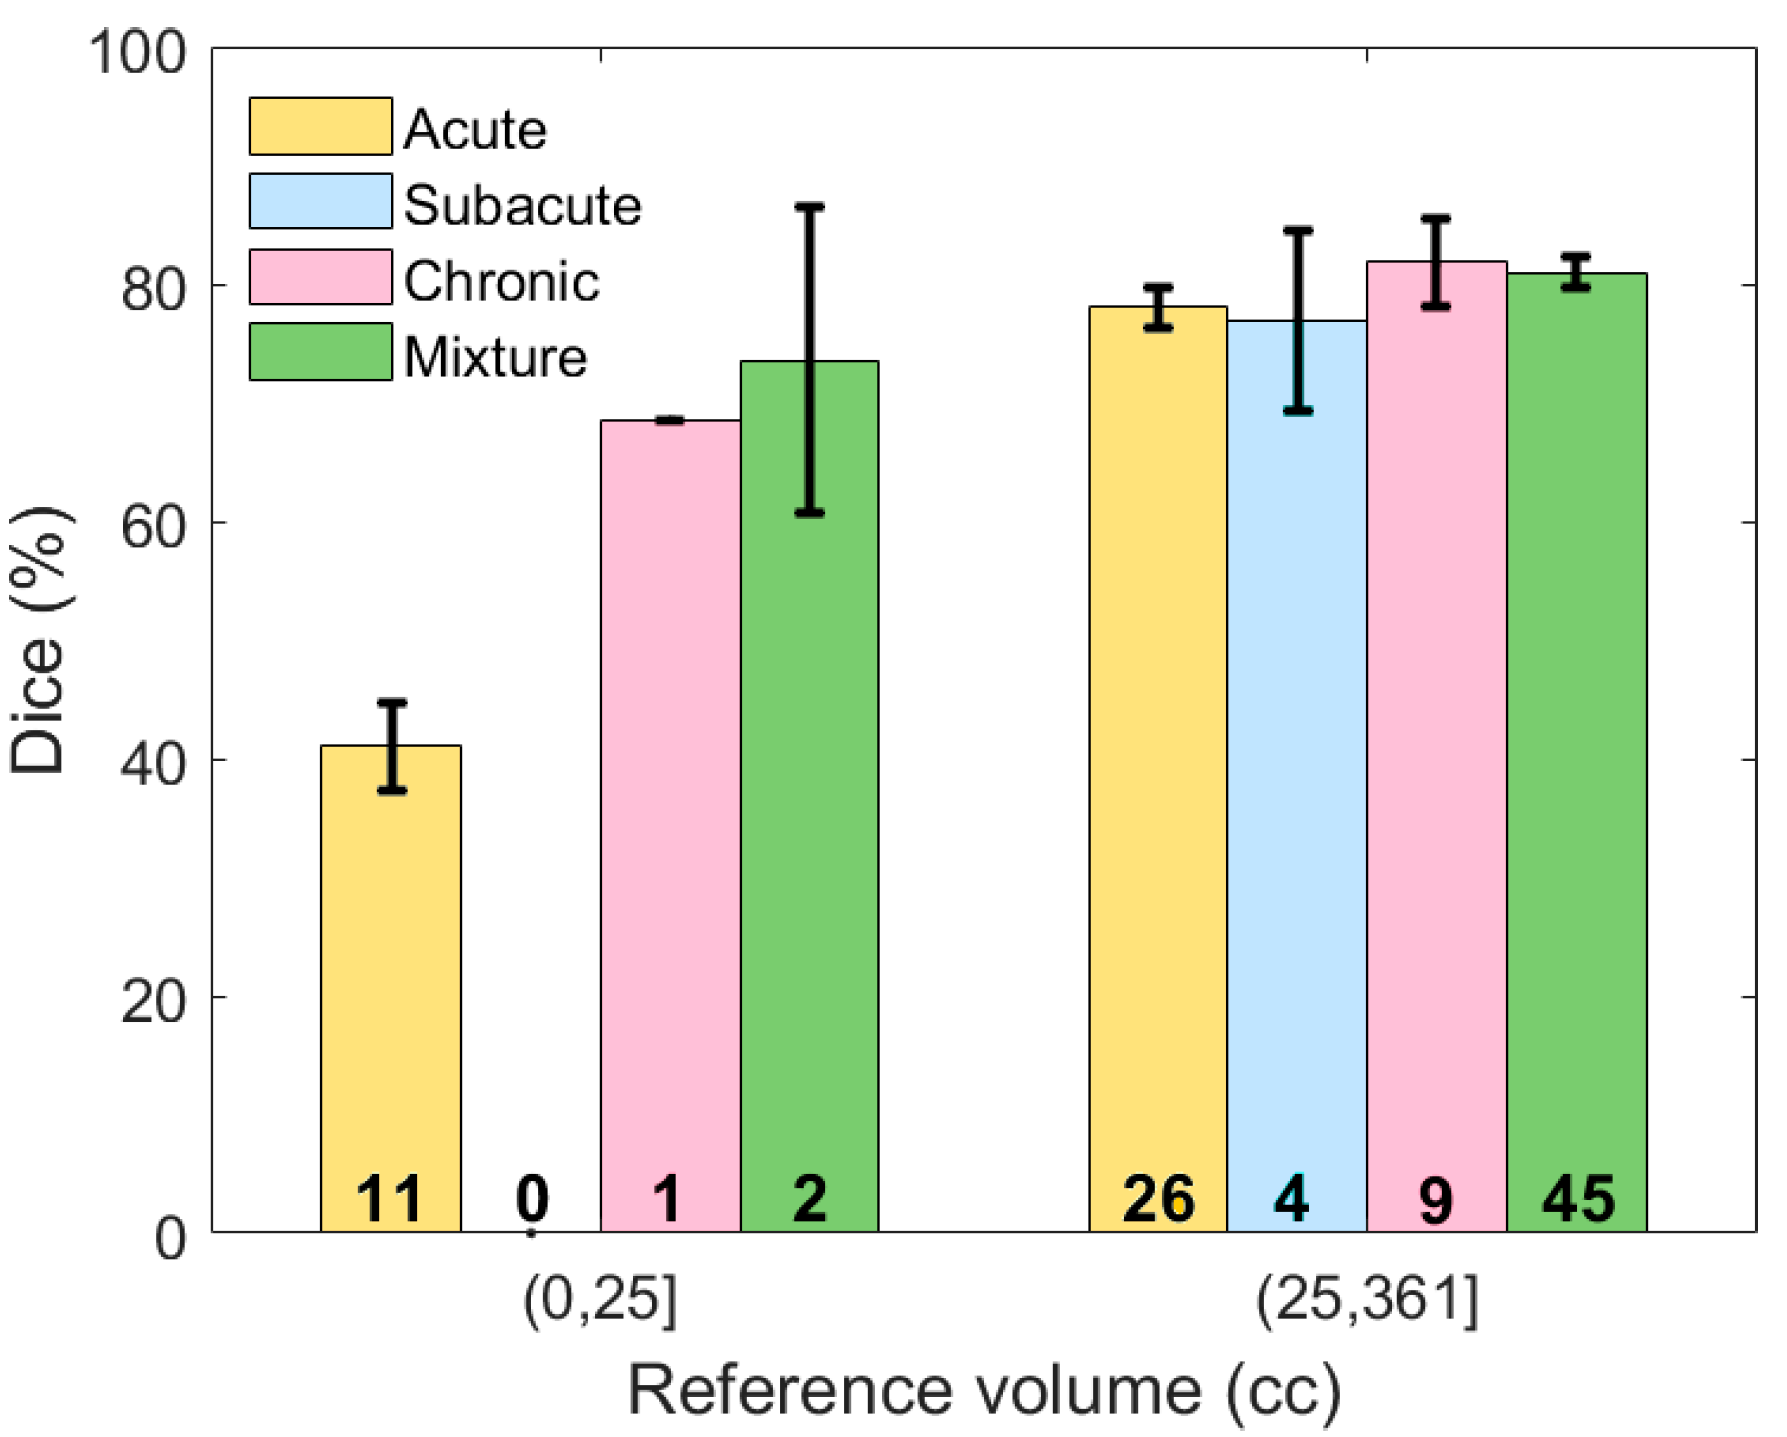

We investigated the performance of the proposed algorithm with respect to subdural hematoma type (

Based on

Table 2, it might be concluded that the overall performance on subjects with acute SDH was lower than the other three types. However, chronic and mixed subdural hematomas tend to be larger in elderly patients because there is more space for the hematoma to expand without symptoms due to brain atrophy. Thus, the proportion of the subjects with acute SDH and less than 25 cc of blood is higher than other types and as discussed earlier, these small hematoma regions are more challenging to detect. Thus, in order to have a valid comparison, the subjects were first grouped according to volume, after which the performance was compared for different types.

Figure 10 shows the average Dice similarity coefficient for each category. Based on this plot, for moderate and severe SDH, the performance of the proposed segmentation algorithm was consistent among different subdural types. We do not have a big enough sample size to either reject or accept performance consistency among different types of the mild (<25 cc) SDH subjects.

Figure 10.

The Dice similarity coefficient based on both the severity and type of hematoma. Error bars represent ±1 standard errors, the 68% confidence interval. The number of samples for each category is shown on the corresponding bar.

Figure 10.